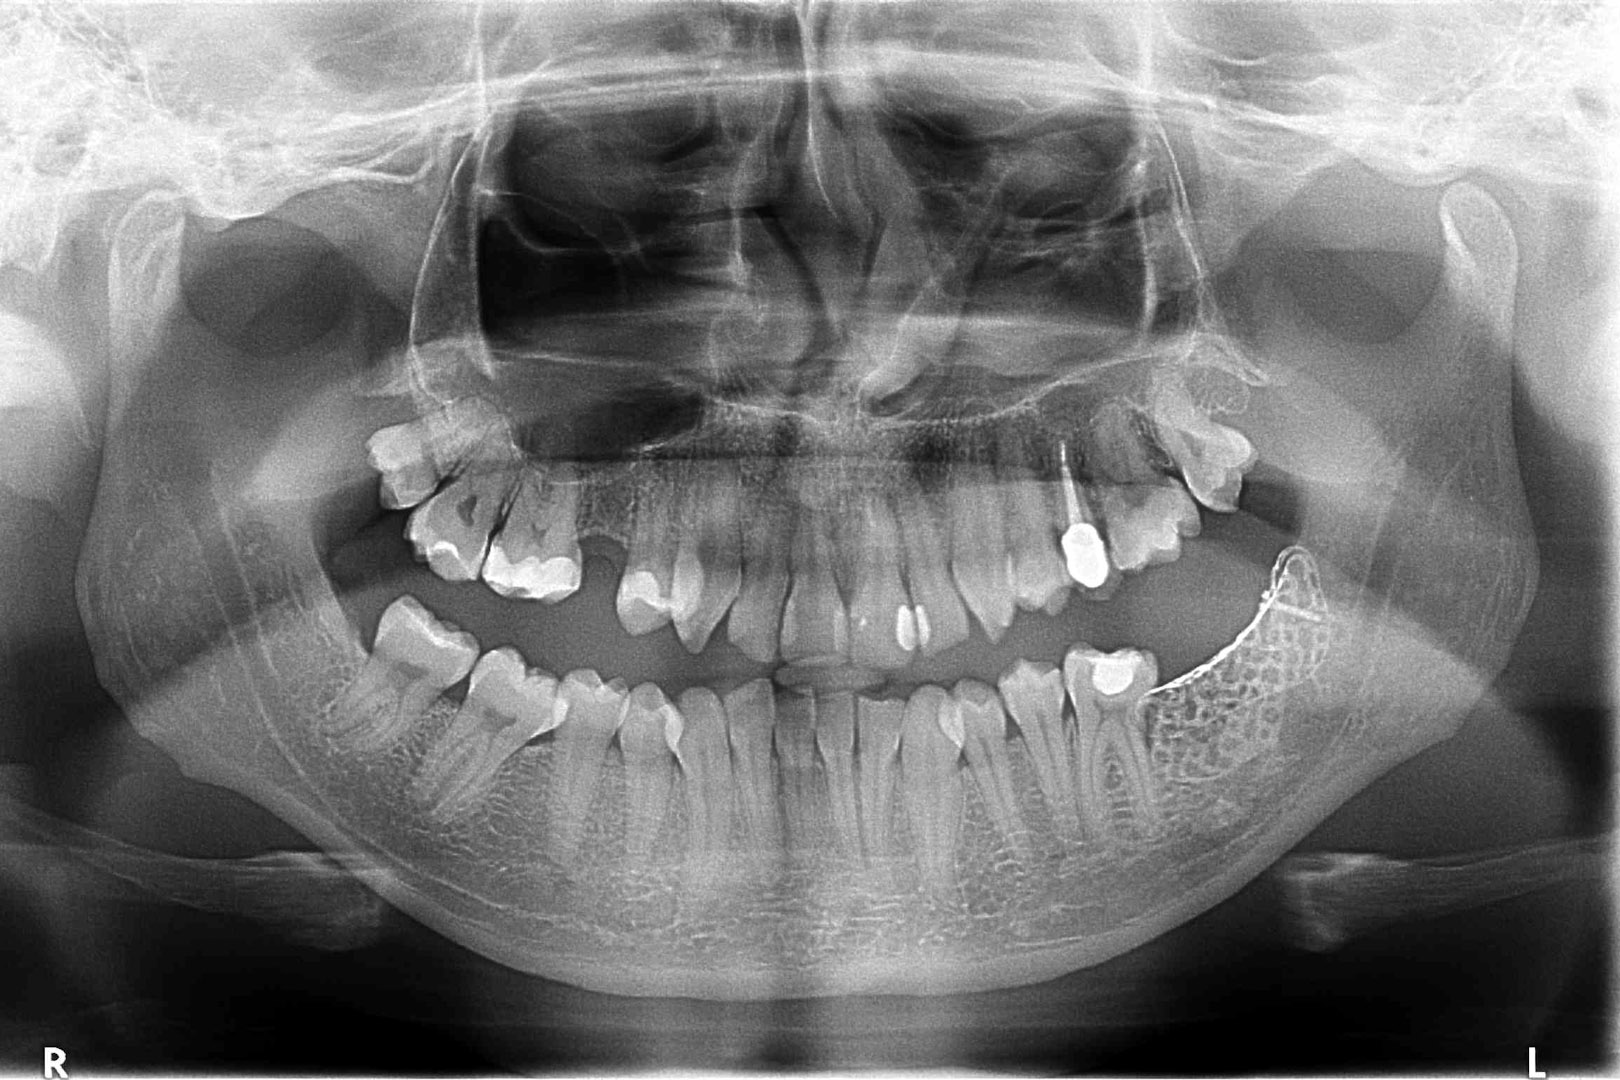

Przed podjęciem leczenia należy określić stopień zaniku kości szczęk oraz żuchwy. W tym celu przeprowadza się badanie kliniczne oraz odpowiednią diagnostykę obrazową pacjenta. Uwzględnia ona zdjęcie panoramiczne OPG jako podstawę dwuwymiarowego obrazowania podłoża kostnego oraz możliwe jest badanie tomograficzne CT lub bardziej precyzyjna tomografia stożkowa CBCT. Opcjonalnie wykorzystywana diagnostycznie tomografia pozwala na bardziej wnikliwą ocenę stopnia zaniku kości w trójwymiarowym, przestrzennym obrazie.

TYPY ZANIKU KOSTNEGO

U pacjentów spotykamy 3 typy zaników kości wyrostka zębodołowego szczęk i żuchwy: